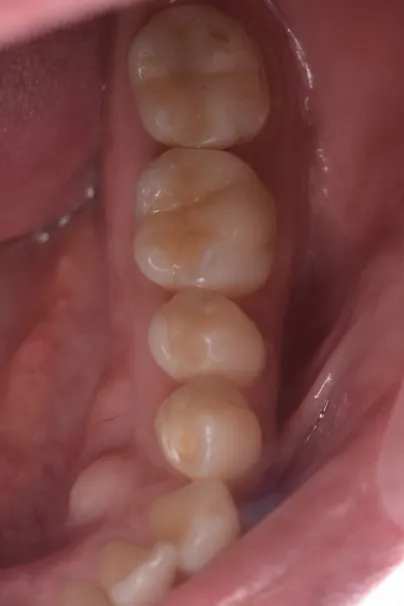

case3

Before

After

治療内容 | 右より、Zrクラウン、CTG+インプラント+Zrクラウン、ラミネートベニア(計3本修復)ホワイトニング |

---|---|

治療期間 | 8ヶ月 |

治療回数 | 15回 |

リスク | 外科的な侵襲、回数や期間的な問題 |

費用(税込) | ¥1,023,000 |